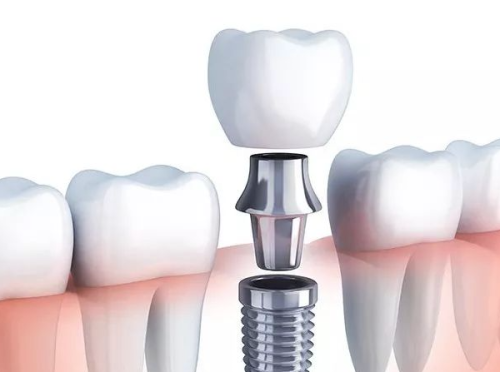

有人可能会有疑问,合肥美奥口腔医院是私立的,它靠谱吗?答案是肯定的。虽然它是私立医院,但却有着严格的医疗资质审核和规范的操作流程。医院的医生都具备丰富的临床经验和专精的知识,他们不断学习和掌握全新的口腔医疗技术,为患者提供良好质的治疗方案。在矫正和种牙技术方面,合肥美奥口腔医院更是有着独特的优势。牙齿矫正采用精良的矫正技术,能够根据患者的牙齿情况制定个性化的矫正方案,让患者在舒适的环境中拥有整齐的牙齿。种植牙技术则引进了国内外精良的种植系统,确保种植牙的稳定性和美观度。

种植牙是合肥美奥口腔医院的特色项目之一。医院拥有精良的种植牙设备和技术,能够为患者提供高质量的种植牙服务。在种植牙过程中,医生会根据患者的口腔情况和身体状况,选择更适合的种植体,确保种植牙的成功几率和使用寿命。说到种植牙,就不得不提到合肥美奥口腔医院的陈国庆医生。陈医生是医院的从业多年种植骨干医生,他拥有多年的种植牙临床经验,擅长各种复杂的种植牙手术。他对待每一位患者都非常认真负责,会耐心地为患者解答疑问,制定更适合的治疗方案。在他的努力下,许多患者都成功地拥有了健康的牙齿。